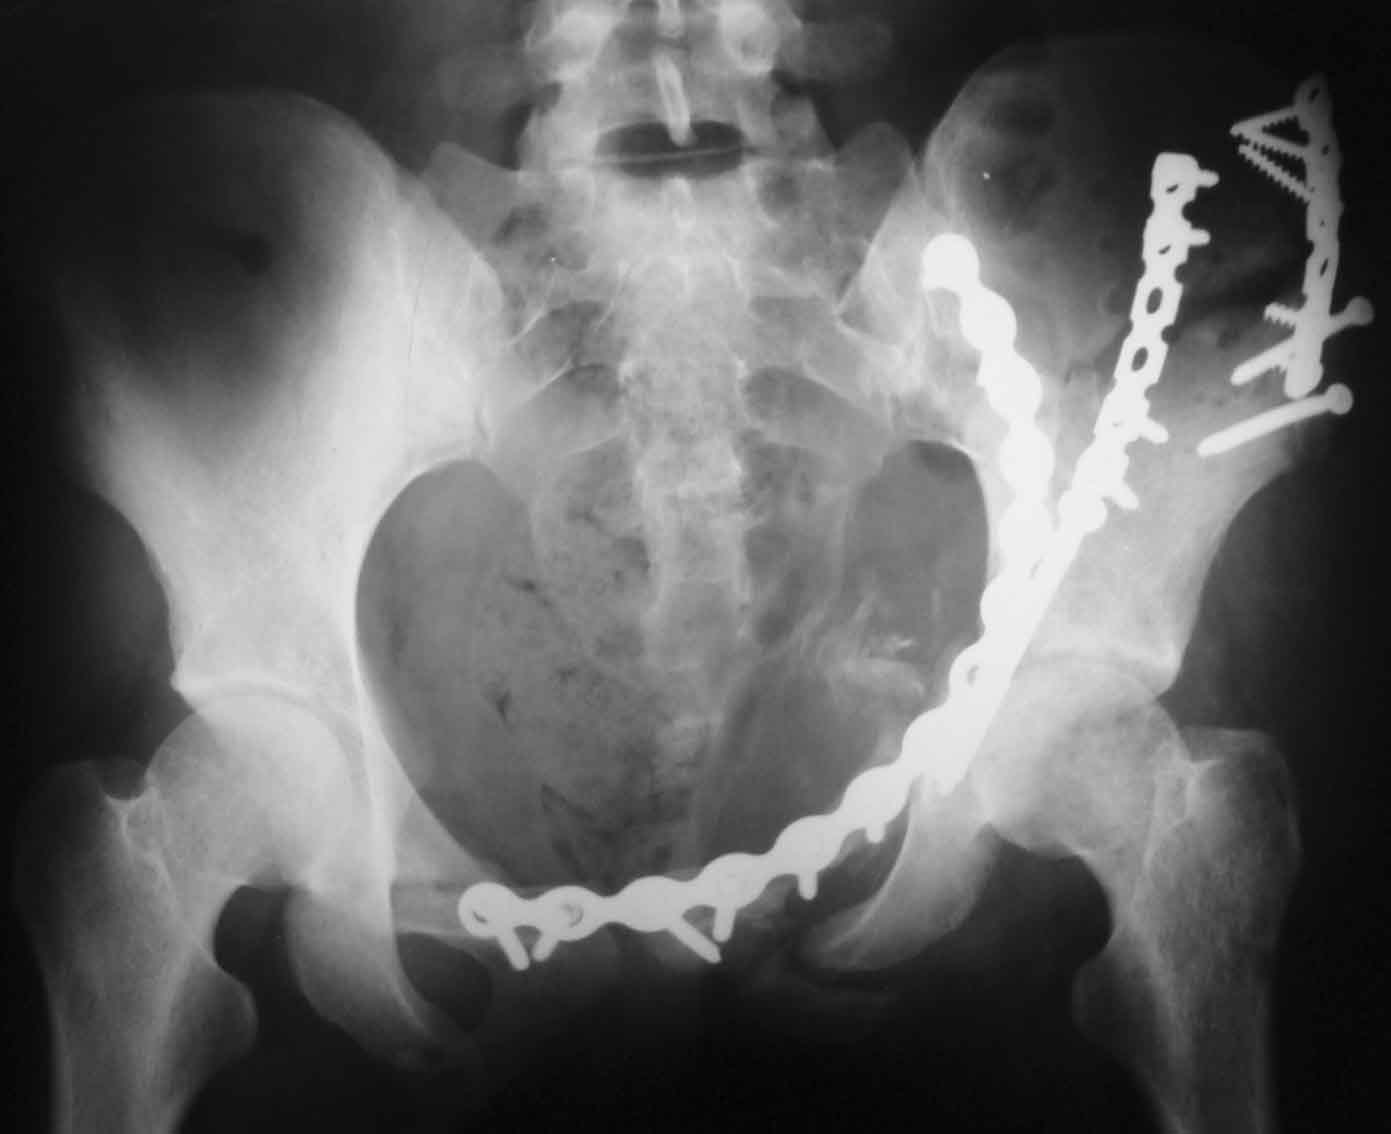

Рентгенограммы после операции

Прямая проекция

A>РО - картина не очень, есть видимость винтов во впадине

По всей видимости, вы имеете в виду канюлированный винт, который проецируется на вертлужной впадине. Та вот, он проведен не через лонную, а седалищную кость. Вертлужная впадина абсолютно интактна. Это хорошо видно на проекции inlet.